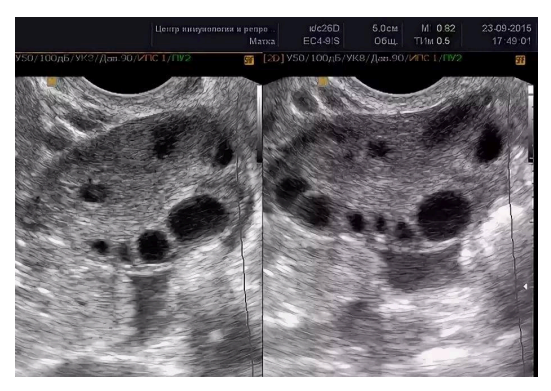

Что показывает УЗИ?

Дополнительную информацию даёт оценка овариального резерва – количества фолликулов в яичниках при УЗИ.

• в возрасте 20–30 лет обычно насчитывается 5–10 и более фолликулов в каждом срезе

• после 35 лет их количество заметно уменьшается

• после 40 лет может оставаться менее трёх фолликулов в срезе. Это говорит о естественном снижении репродуктивного потенциала, но не даёт точного прогноза по срокам менопаузы.